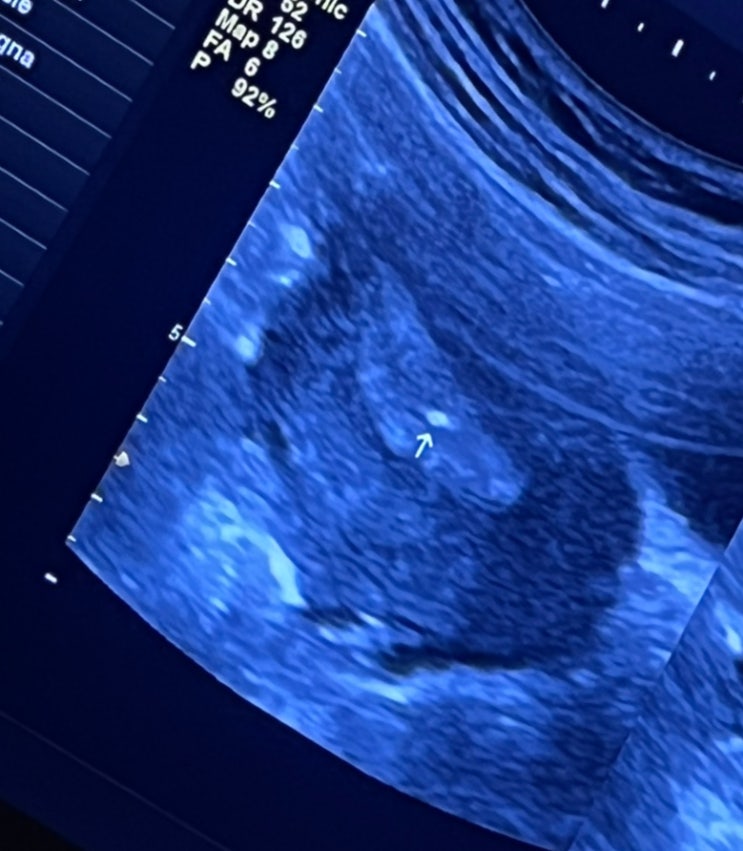

임신 12주 1차 기형아 검사 초음파 결과, 1차 기형아검사 성별

임신의 안정기라 불리는 임신 12주차에 진입한 래용? 입덧은 잔잔히 계속되고 있지만 래용이가 안정기에...